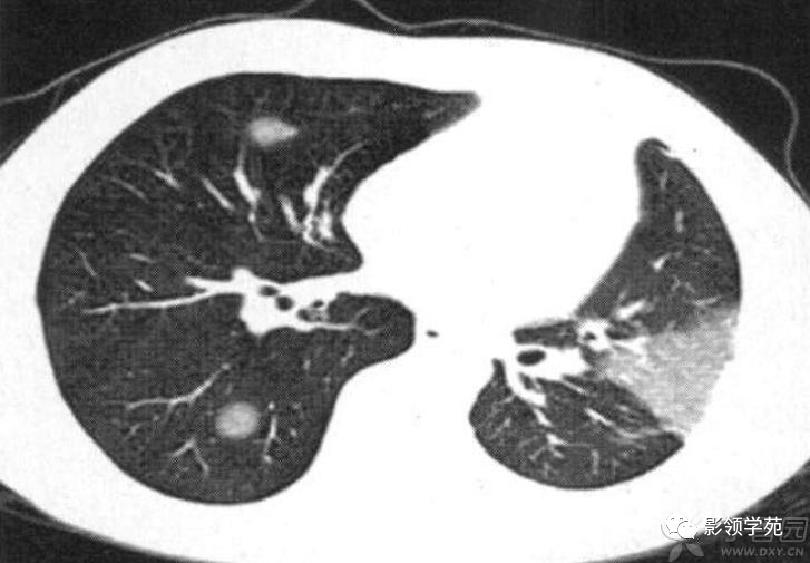

肺内多发结节和肿块是肺Wegener肉芽肿最常见的影像征象,表现为两肺散在分布、多发大小不等类圆形结节或肿块影,以两肺中下野分布多见。部分结节和肿块内可见空洞,洞壁多较厚,内缘光滑或不规则,空洞呈边缘性强化。合并感染时空洞内可形成液-气平面。结节或肿块周围一般都有较短毛刺,部分病灶有长毛刺与邻近的胸膜相连,表现为胸膜凹陷征。这与病理上结节周围存在大量成纤维细胞以及以纤维化形式愈合有关。

结节或肿块周围可见晕轮征、供养血管征。晕轮征提示肺结节或肿块出血,CT表现为结节或肿块周围磨玻璃密度影;供养血管征CT表现为血管影进入结节或肿块内,提示病变以血管为中心生长。

Pretorius等研究Wegener结节出现后一般不再增大,短期内大小无明显变化,或经激素和免疫*制剂抑**治疗后肺部病变可逐渐缩小、减少,大部分结节、实变可完全吸收,在逐渐缩小过程中边缘由模糊变清楚,较大结节边缘可出现针刺状突起,最后变为星芒状纤维灶;而结节性空洞的洞腔可由小变大,洞壁由厚变薄,经治疗后短期内洞腔逐渐缩小以至闭塞,最后变为星芒状纤维灶;动态影像观察还发现原结节愈合后,其他部位又可出现大小、形态、密度与原有病灶相似的新病灶,此即所谓“游走性”的特点。

病例7:经治疗CT随访:左肺下叶片状磨玻璃密度影,右肺下叶及左肺下叶多发结节灶。

病例9:右下肺结节,病灶后份可见结节状钙化,边缘光滑,周围无卫星病灶。(钙化主要出现在治疗后肿块的边缘,相对较少见)